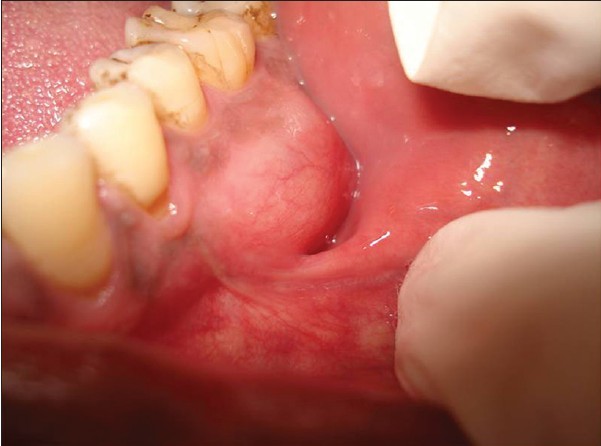

An Opening for Gum Disease

It's critical to thoroughly brush the area where the gums meet the teeth and floss between the teeth to keep the entire gingival sulcus clean. When plaque is allowed to build up on the gums at the base of a tooth, it can cause gingivitis, when the gums become inflamed and irritated. Luckily, you can reverse gingivitis with excellent oral care. However, if the plaque continues to build, the inflammation can lead to the gums detaching from the tooth, causing the space between the teeth and gums to deepen and allow even more plaque to accumulate. This deepening of the sulcus, also referred to as the development of a periodontal pocket, is an early indicator for periodontal disease. The National Institute of Dental and Craniofacial Research classifies periodontal disease as a site with gum attachment loss of at least 3 millimeters and a pocket depth of at least 4 millimeters.